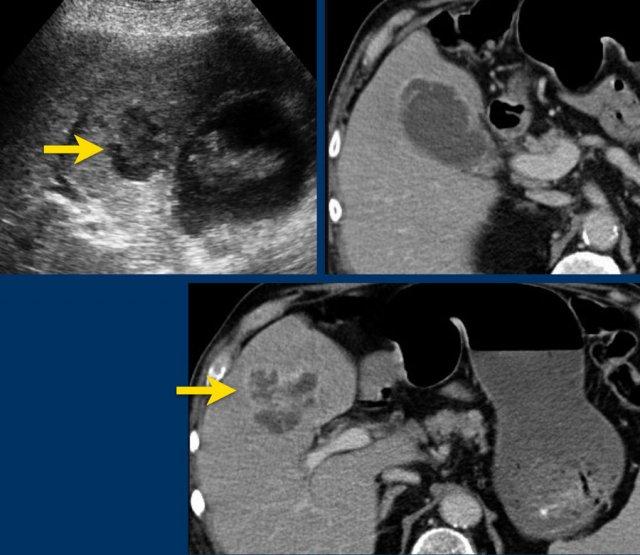

Viêm túi mật khí thũng. Siêu âm cho thấy khí ở đáy túi mật (đầu mũi tên). CT xác nhận có khí cả trong lòng và trong thành túi mật.

Viêm túi mật xuất huyết. Siêu âm chỉ cho thấy một khối giống cặn lắng. CT cho thấy máu tăng tỷ trọng trong lòng túi mật và thành túi mật không đều. Phẫu thuật cắt túi mật rất khó khăn về mặt kỹ thuật.

Viêm túi mật xuất huyết

Viêm túi mật xuất huyết là thể hiếm gặp, xảy ra khi hoại tử thành túi mật dẫn đến chảy máu trong lòng túi mật.

Thể này gặp nhiều hơn ở bệnh nhân đang điều trị bằng thuốc kháng đông.

Siêu âm thường không đặc hiệu nhưng có thể cho thấy một khối lớn dạng cặn lắng và thành túi mật không đều.

CT cho thấy các khối tăng tỷ trọng, không suy giảm tỷ trọng trong lòng túi mật (hình).

Do xuất huyết là hậu quả của hoại tử thiếu máu cục bộ thành túi mật, phương pháp dẫn lưu qua da không được ưu tiên trong trường hợp này, mặc dù phẫu thuật cắt túi mật cũng có thể gặp nhiều khó khăn.

Đây là một trường hợp viêm túi mật xuất huyết khác ở bệnh nhân đang dùng salicylate.

CRP là 150.

Phẫu thuật cắt túi mật nội soi cấp cứu được thực hiện ngay.

Tình trạng phình to túi mật (hydrops) được xác nhận và chọc hút trong mổ cho thấy máu.

Phẫu thuật có biến chứng là khối máu tụ lớn sau mổ.